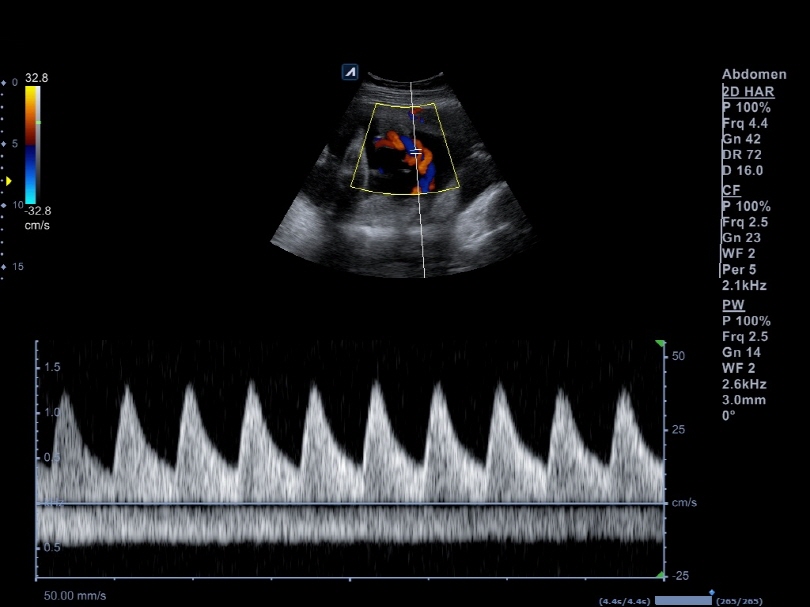

C1-6CT

C-Architecture (PowerView™)

Convex transducer (1-6MHz)

Application:

Abdomen, EM, Gynecology, Obstetrics